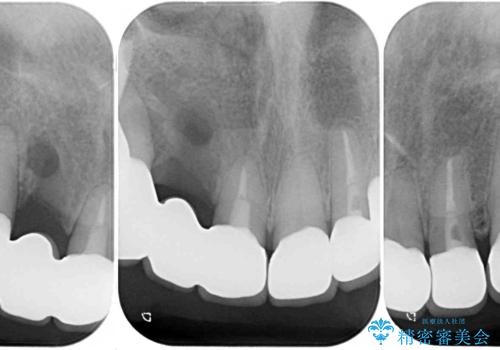

大臼歯部は、上下左右ともに咬合により問題が生じており、骨格的な問題から積極的な治療をするべきか判断の難しい状況でした。

臼歯部は痛みが生じている歯に絞って処置を行い、それ以外については手を加えず、現状維持を心がけることとしました。

臼歯部は今後抜歯が必要となった際に、インプラントにより咬合を構築していくこととしました。今回の治療においても、今後の臼歯部の治療に対応できるよう治療計画を立案しています。